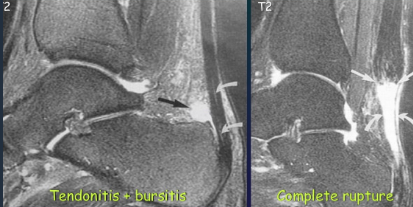

Achille's tendon rupture